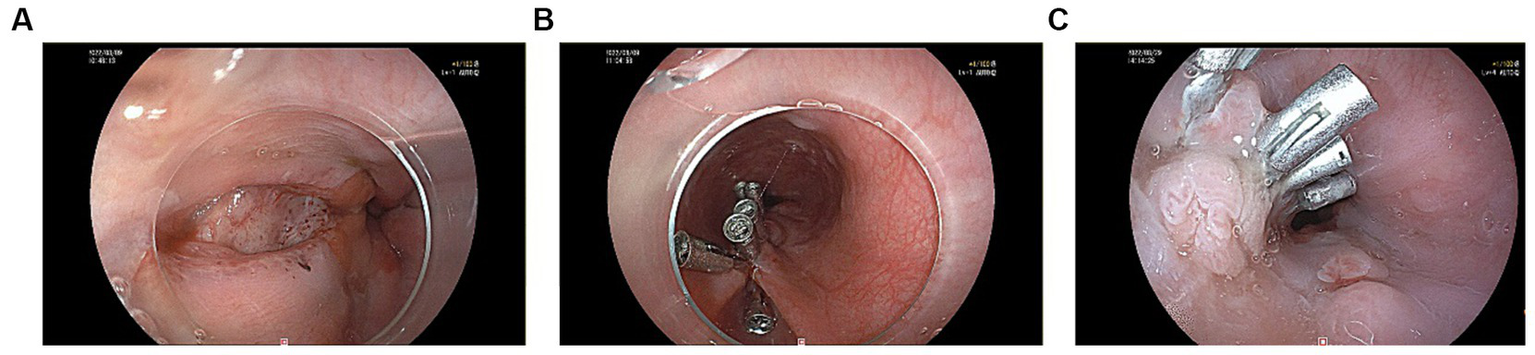

A 60-year-old male patient, who was in a state of good health with no significant medical or familial history and no specific complaints, had been scheduled for a screening colonoscopy. The patient started bowel preparation at around 22:00 pm and finished consuming 250 mL of mannitol and 2 L of water at around 01:00 am. Half an hour later, the patient vomited twice and then developed symptoms such as upper abdominal pain, abdominal distension, and chest tightness. Upon physical examination, decreased breath sounds and dullness upon percussion were observed over the left lower lung without jugular venous distention and cardiac murmurs. Laboratory studies revealed elevated inflammatory markers [White Bloodcell Count (WBC) 16.88×109/L, hypersensitive C-Reactive Protein (hsCRP) 44 mg/L, Procalcitonin (PCT) 3.03 ng/mL]. Furthermore, biochemical examination showed no abnormal electrolytes or liver and renal function. A thoracic computed tomography (CT) scan revealed the presence of an esophageal-mediastinum fistula and pleural effusion on the left side (Figure 1). A diagnosis of BS was strongly suspected, leading to the immediate performance of gastroscopy in case of stable vital signs. The patient underwent gastroscopy at around 10:30 am, during the procedure, a longitudinal laceration (length approximately 50 mm) was observed in the esophagus, specifically located from 35 cm from the incisors to the cardia on the lesser curvature side, which was suspected to be the site of perforation (Figure 2A). Closure of the defect was accomplished using a total of 6 titanium clips (Figure 2B). Time line of events from start of prep to diagnosis and intervention as show as Figure 3. After surgery, patient was hemodynamically stable and transferred to the general ward. Following continuous left chest drainage, administration of anti-infection measures, and nutritional support, a re-examination of the gastroscope conducted 20 days after hospitalization revealed a well-closed, scar-like hyperplasia at the site of the initial rupture in the lower esophagus (Figure 2C). Repeat thoracic CT showed resolution of pleural effusion (Figure 4). Laboratory test revealed 5.06 × 109/L WBC, 12 mg/L hsCRP and 0.04 ng/mL PCT, respectively. He recovered well and was discharged from hospital 3 weeks later.

Figure 2

(A) A longitudinal laceration located in the esophagus was seen under gastroscopy. (B) Clamping the esophageal chasm with 6 titanium clips. (C) A well-closed, scar-like hyperplasia at the site of the primary rupture of the lower esophagus.